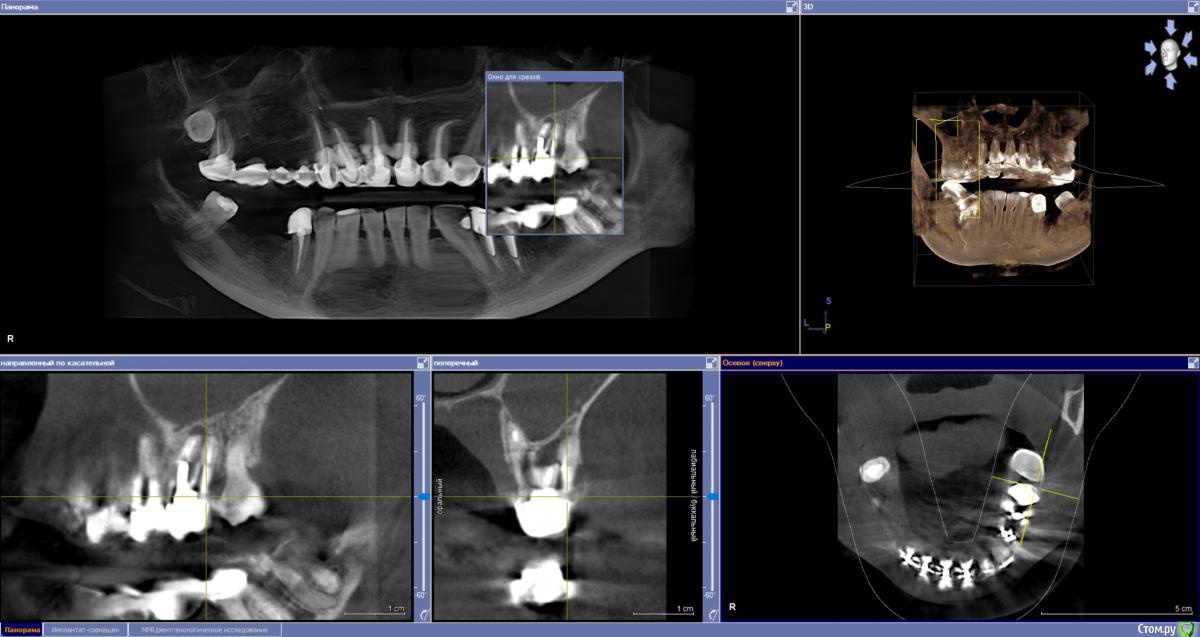

sabik Опубликовано 13 марта, 2019 Поделиться Опубликовано 13 марта, 2019 Хотела б услышать мнение по поводу возможности установки имплантов, ходила в несколько клиник, все говорят разное, общее только то, что на КТ видно, что нет кости вообще, проблема с верхней пазухой,нужна операция лор, еще вопрос можно ли повторить этот мост наверху при отсутствии трех зубов? Не хотят браться за меня нигде Еще беспокоит тупая ноющая боль время от времени, на снимке слева внизу, причину не находят. Подскажите, есть ли зубы на удаление, и какие проблемы видно в общем? Ссылка на комментарий

sabik Опубликовано 14 марта, 2019 Автор Поделиться Опубликовано 14 марта, 2019 Болтается мост сверху, на снимке слева, и беспокоит тупая боль снизу на этой же стороне, жую почти 2 года другой стороной, нужно менять коронки и где возможно установить импланты. Хочу услышать мнение профессионалов по снимку, что можно сделать в моей ситуации. По КТ кости не хватает нигде. Ссылка на комментарий

sabik Опубликовано 23 марта, 2019 Автор Поделиться Опубликовано 23 марта, 2019 Выкладывайте срезы КТПо инструкции с сайта не смогу выложить срезы, нет соответствующей папки (Dicom), но сделала скриншоты (прикреплены к сообщению) проблемных мест в программе. Если не совсем то, скажите, как лучше сделать скриншоты (или видео). Очень нужно мнение специалистов! Ссылка на комментарий

kramer Опубликовано 23 марта, 2019 Поделиться Опубликовано 23 марта, 2019 Источник боли с правой стороны на нижней челюсти пока неясен. Что касается верх право, чтобы ставить имплантаты, надо предварительно делать синус-лифт, до синус-лифта надо приводить пазуху в порядок с помощью ЛОР врача Ссылка на комментарий

Nazim_NV86 Опубликовано 23 марта, 2019 Поделиться Опубликовано 23 марта, 2019 Возможно ли поставить импланты снизу справа? Возможно. А слева какая ситуация, есть ли кисты. удалять надо зубы или нетПроблемы есть. Нужно во рту смотреть и томограмму. Вы срезы не те выкладываете. Этот Galileos только с диска читается. Ссылка на комментарий

sabik Опубликовано 2 апреля, 2019 Автор Поделиться Опубликовано 2 апреля, 2019 Предлагают два варианта постановки имплантов справа внизу: первый вариант - поставить 2 импланта вместо 5 и 6 зуба, с подсадкой кости, расщеплением гребня, а второй вариант- 2 импланта вместо 5 и 7 зуба, с подсадкой кости только на 5 зубе, а на место 7-го имплант сразу ровно поставленный, и позже мост . 7 зуб живой, но с наклонном, боль есть тупая, говорят может он один там и нагрузка идет на него, не знаю, из-за этого может болеть он временами или нет, перидонтальная щель расширена чуть тоже. Как считаете, какой вариант имплантации лучше? Ссылка на комментарий